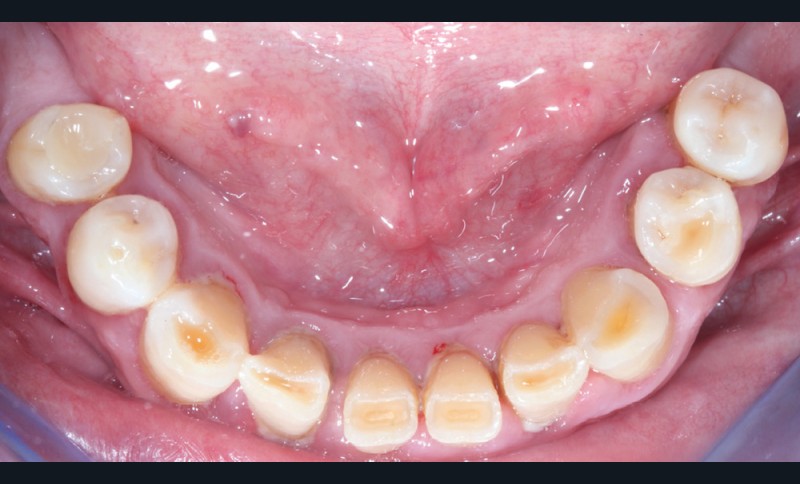

Après une étude prothétique [4, 5], il est décidé de procéder à l’extraction des dents maxillaires résiduelles (sauf une molaire qui servira pour enregistrer l’occlusion et qui sera avulsée dans un second temps), avec une implantation immédiate de 6 implants maxillaires et une mise en charge immédiate d’un bridge provisoire. Les implants se distribuent sur l’arcade ; des aménagements sous-sinusiens ne sont pas nécessaires (fig. 4 à 6).

Des implants mandibulaires postérieurs sont également programmés dans la même séance.

La réhabilitation bi-maxillaire est envisagée selon le concept de l’arcade courte, intéressant jusqu’aux premières molaires. La prise en charge a débuté par une motivation à l’hygiène, et une explication des techniques de prophylaxie, avec notamment la remise d’une brosse à dents électrique et des têtes de brosses adaptées et des brossettes interdentaires de tailles différentes (fig. 7).